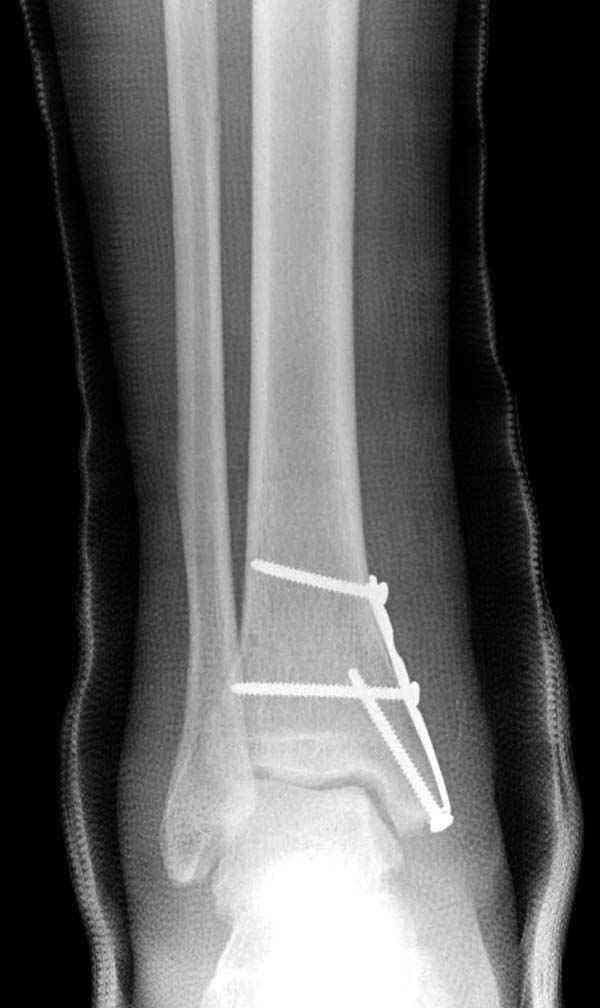

Описанная вами техника "Внутренняя лодыжка фиксирована по Веберу, наружная реконструктивной пластиной с наложением болта-стяжки" существует, но этот подход морально устарел, и применяется очень редко, только при отсутствии имплантов.

Нет первичных снимков, перелом очень низкий и под большим сомнением диагноз разрыва синдесмоза. Медиальная сторона отрепонирована на "хорошо" и, по-видимому, прорезание проволоки произошло во время операции. Без снимков трудно судить о высоте малоберцовой, а лодыжка находится в варусе. Лагирование получилось, но возле тонких шурупов передне-задний шуруп выглядит немного тяжеловато.

Во всех руководствах АО имеется описание техники применения низкопрофильных пластин 1/3 трубки, которые могут быть применены для фиксации наружной лодыжки. Фиксацию проводят кортикальными 3.5 мм шурупами, и если дистальная фиксация недостаточная, тогда усиливают конструкцию созданием hook plate. Сгибая конец пластины на последнем отверстии, внедряют его в дистальный отдел, и тем самым создается дополнительная фиксация.

Современные преконтурированные пластины не имеют таких недостатков, и разделяются на правые и левые, а также на латеральные и задние. Множественные дистальные шурупы 2.7 мм уменьшают подкожное раздражение, и такой имплант можно оставить на долгий срок без удаления.

В лечении синдесмоза шурурпы легче установить, и, тем более, они намного дешевле, чем болт-стяжка. От болтов еще и часты осложнения - медиальные пролежни.

При лечении синдесмоза количество шурупов не имеет значения. Два через три кортекса или один через все кортикальные слои механически одинаковы.

Здесь несколько частных случаев: перелом голеностопа со сравнительными снимками и разрыв синдесмоза, а также медиальная Hook пластина.